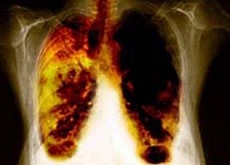

Il ministro della Salute Ferruccio Fazio «è risultato positivo al test della tubercolosi, come del resto il 12% della popolazione italiana». Ad annunciarlo è stato oggi il direttore del dipartimento malattie infettive dell’Istituto superiore di Sanità, Giovanni Rezza, durante la giornata studio «Tbc a Roma: che fare?», organizzato dal Codacons e da Articolo 32.

Rezza ha comunque precisato che Fazio «non si sta curando, non ne ha bisogno. Le persone positive – spiega – se hanno infezione latente, non sono a loro volta contagiose e non devono curarsi, a meno che in rari casi, sviluppino dei sintomi». Rezza ha rassicurato che l’Italia resta un paese a

bassa incidenza di tubercolosi. Tornando al caso Fazio, ha precisato: «Facendo il medico può essere stato facilmente contagiato nei reparti. Ma c’è un rischio, di essere contagiati a livello di comunità anche se nella stragrande maggioranza dei casi questo rischio non si traduce assolutamente in malattia»

D’altra parte secondo il resposnabile Iss non c’è nessun allarme Tbc in Italia: «i dati, anche in riferimento agli altri Paesi europei, sono nella media, nonostante l’ampio afflusso di immigrati ad alto rischio Tbc» ha detto Rezza.